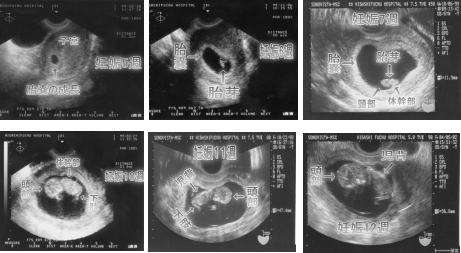

◇妊娠1ヶ月(卵体期)0〜3週 0.8〜1.6o 受精から着床、胎盤を形成 ◇妊娠2ヶ月(胎芽期:器官形成期)4〜7週 2.5〜2.0p 外胚葉と内胚葉という2つの細胞層ができ(妊娠4週)、体のいろいろな組織や器官となっていく。 ◇妊娠3ヶ月(ここから胎児期)8〜11週、7〜9p・・約10〜20g:人間らしい形になってくる。 ◇妊娠4ヶ月(12〜15週)14〜17p・・約100g:各臓器の基本的な形がほぼ完成。顔のつくりが整ってくる。 ◇妊娠5ヶ月(16〜19週)約25p・約250g。妊娠中期、安定期に入る。聴診器で心音をきくことができる。 ◇妊娠6ヶ月(20・21・22・23週)約30p・約650g(大きさに個人差がでてくる) ◇妊娠7ヶ月(24〜27週)約35p・約1000g。超早産:妊娠22週より28週未満の間の分娩 ◇妊娠8ヶ月(28〜31週)約40p・約1500g。妊娠後期に入る。 ◇妊娠9ヶ月(32・33・34・35週)約45p・約2200g ◇妊娠10ヶ月(臨月)(36〜39週)約50p・約3000g。早産:妊娠24週より37週未満の間の分娩 正期産(妊娠37〜41週で生まれる)・満期産ともよぶ。 ◇妊娠40週の最初の日が妊娠280日目、出産予定日となる (妊娠42週以降の出産は過期産とよぶ)

◇妊娠3ヶ月(ここから胎児期)8〜11週、7〜9p・・約10〜20g:人間らしい形になってくる。 筋肉、骨格のはじまり。顔と首が発達し、黒目がわかる。大脳皮質の神経細胞の生成がはじまる。頭部と体幹部の区別をつけることができる。鼻や口唇(4〜8週)、まぶたができる。心拍動がしっかりしてくる。口蓋が形成される(6〜12週)。9週以降には手足の区別がつき、指が完全に分かれ、耳が形成される。腎臓が機能しはじめる。 人間らしい形になってくる

◇妊娠4ヶ月(12〜15週)14〜17p・・約100g:各臓器の基本的な形がほぼ完成。顔のつくりが整ってくる。 脳が急成長し、神経細胞の髄鞘化がはじまる。間脳や大脳辺縁系が発達してくる。骨格がしっかりしてくる。各臓器の基本的な形がほぼ完成。手足の形、外性器の形もできあがる。顔のつくりが整ってくる。耳たぶができる。 羊水を飲み、おしっこする。